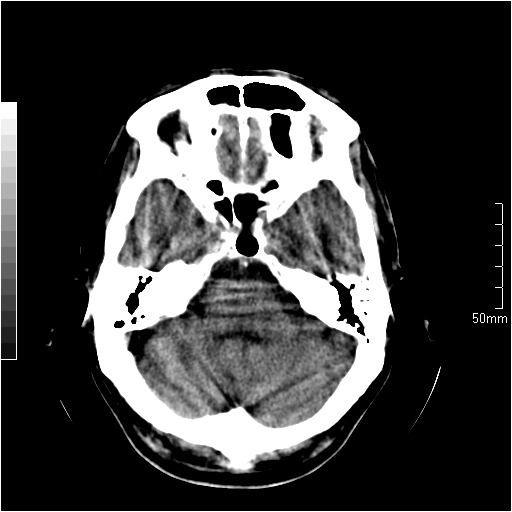

以下是引用天南地北在2007-6-25 12:39:00的发言:[br]有占位效应[br]支持术后复发

以下是引用zjzjr在2007-6-25 12:38:00的发言:[br]左侧复发,右侧转移。